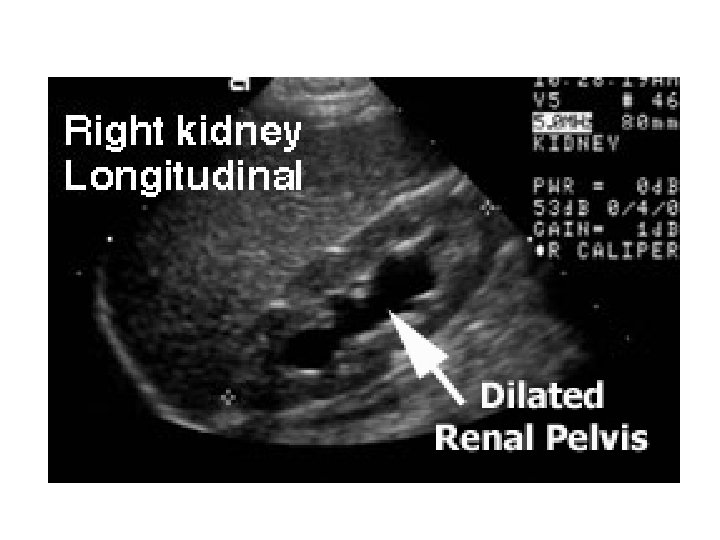

Prenatální diagnostika • ledviny jsou zobrazitelné ultrazvukem od 12. -15. týdne • cílem je odhalení vývojových vad – dysplazie ledvin, poškození funkce ledvin, hypoplázie plic • Oligohydramnion – primární poškození ledvin, sekundárně plic (součást syndromu Potterové ) • Cystická dysplázie ledvin – zvýšené riziko rozvoje Wilmsova nádoru (nefroblastomu) • Hydronefróza – vznik při obstruktivních nefropatiích

Vyšetření ledvin • • nativní rtg snímek sonografie vylučovací urografie ascendentní pyelografie scintigrafie clearence CT, MR

Ultrazvuk ledvin http: //lunar. thegamez. net/medical/ultrasound-sonography/ru-ultrasound-image-description-kidney-640 x 480. jpg http: //www. genesis-ultrasound. com/images/renal-ul-image. jpg